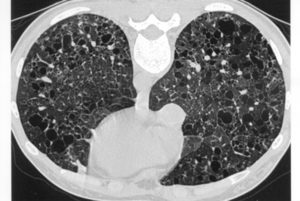

Сотовое легкое

Определение. Это рентгенологическое понятие, указывающее на наличие кист, часто диффузных, в обоих легких, обычно имеющих 0,5—2 см в диаметре, относительно тонкостенных и не заполняющихся контрастом при бронхографии. Нередко имеются дополнительные узелки или очаговость.

«Сотовое легкое» — это патоморфологический синдром, для которого характерно образование в легочной ткани «сотов», или маленьких полостей, воздушных кист, у которых толстые стенки, из фиброзной соединительной ткани. Толщина этих стенок может достигать 3 мм.

Иными словами, эти полости – следы «отбушевавшего» аутоиммунного воспаления. В норме легочная ткань представляет собой «дышащую альвеолярную пену», а «соты» — не что иное, как головешки и угли погасшего костра. Этот феномен диагностируют рентгенологически, и его появление – неблагоприятный сигнал.